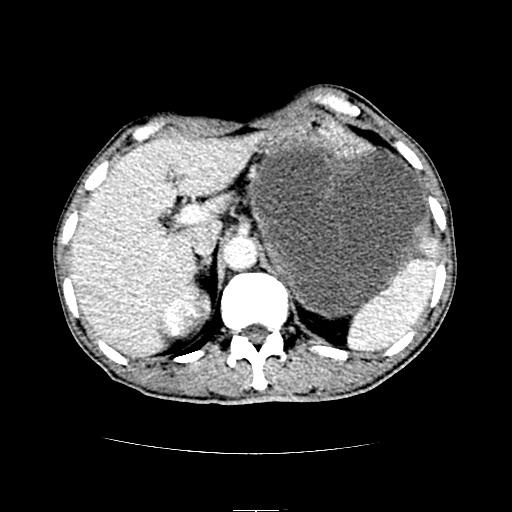

胰尾部巨大囊性病变,胰腺体积增大.左肾吉氏筋膜增厚.1慢性胰腺炎伴随假性囊肿2左肾囊肿

胃脾胰之间一巨大囊性影,内可见间隔,应为囊实性占位:多考虑:1 网膜巨囊腺瘤?。2 左肾小囊肿